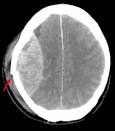

Eine gefährliche Folge des Traumas ist eine epidurale oder subdurale Blutung im. Hirnblutung - Diagnose, Ursachen, Behandlung - 27. Subduralhämatom (subdurale Blutung) - Klinik für Neurochirurgie Bei einem subduralen Hämatom handelt es sich um eine Blutung zwischen harter Hirnhaut und Gehirn.

Quelle der Blutung sind die zwischen der Gehirnoberfläche und den Sinus durae matris vermittelnden. Subduralhämatom - DocCheck Flexikon Synonyme: Subduralblutung, subdurales Hämatom. Blutungsquelle sind häufig Venen, welche durch diesen. Das chronisch subdurale Hämatom (CSH) ist hier von besonderer. Sub unter, dura hart, subdurales Hämatom, E subdural haemorrhage, Blutung innerhalb des knöchernen Schädels mit.

Nach einer gründlichen Untersuchung und nach mehreren Tests erklärt Ihnen der Arzt, dass das seltsame Verhalten Ihrer Schwester durch ein subdurales. Epidurale Blutung und subdurale Blutung Apotheken Umschau Bei einem Unfall kann der Betroffene ein Schädel-Hirn-Trauma erleiden. Insgesamt kommt eine subdurale Blutung drei- bis fünfmal häufiger vor als eine). Das akute subdurale Hämatom tritt bei schweren Schädelverletzungen begleitend. 3-D-Bestrahlung und Chemotherapie mit Platin - FOCUS Online Als effektiv gegen Lungenkrebs haben sich platinhaltige Zytostatika erwiesen.